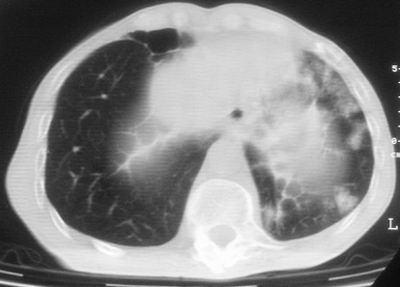

标题: CT11864:男,47岁,反复咳嗽、咯痰、咯血3年,请分析. [打印本页]

患者,男,47岁,反复咳嗽、咯痰、咯血3年,再发5天。痰培养未找到真菌、抗酸杆菌、癌细胞。

左肺上叶体积明显缩小,其内见多发透光区,纵隔向左侧移位,左肺下叶多发班片状病灶,边界模糊,1左肺上叶先天肺发育不全,2左肺下叶肺炎,

左肺上叶结核伴肺纤维化,纵隔移位,左肺下叶感染性病变,建议抗炎抗结核后复查,双肺气肿.

以下是引用xulianj在2008-2-25 21:01:00的发言:[br]左肺上叶结核伴肺纤维化有霉菌球形成,纵隔移位,左肺下叶感染性病变,建议抗炎抗结核后复查,双肺气肿.

考虑:左肺慢纤伴霉菌球形成、双肺全小叶型肺气肿。

1)考虑为:左肺上叶肺结核(空洞形成),伴左下肺感染;不排除霉菌感染可能。2)肺气肿。

左肺上叶结核伴肺纤维化空洞形成并左肺下叶感染,纵隔牵拉移位,建议作进一步检查排除左侧肺霉菌感染可能。